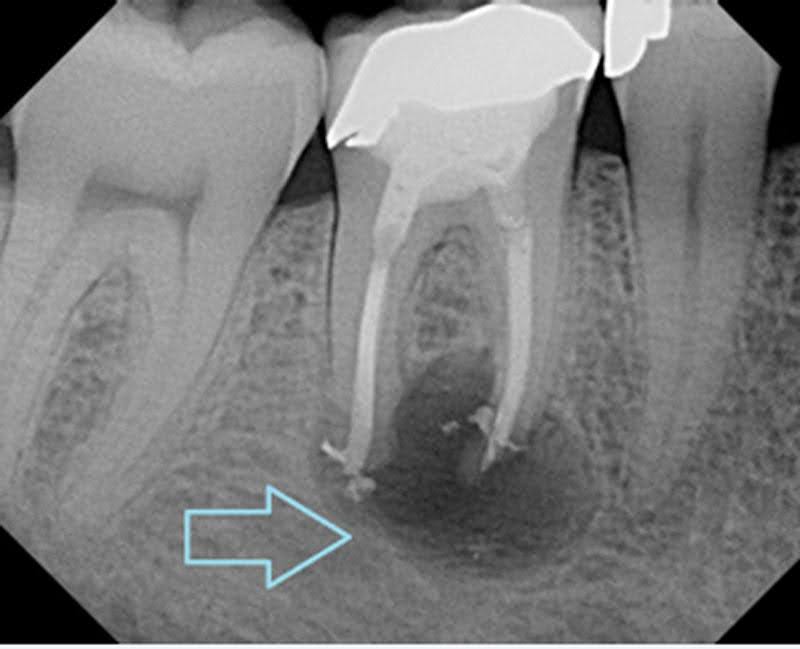

4. Infection or Abscess

A dental infection can weaken the bone and tissue surrounding a tooth, causing it to become loose.

This is a serious condition that requires prompt treatment.

Treatment:

- Root canal

- Antibiotics

- Extraction (if necessary)